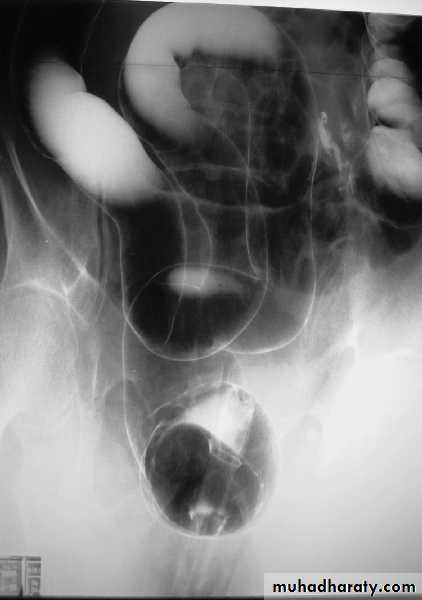

Toxic megacolon

toxic mega colon

Radiological features of toxic megacolon :

• The colon (typically transverse colon) becomes dilated to at least 6 cm (usually greater). There is additional loss of haustral markings